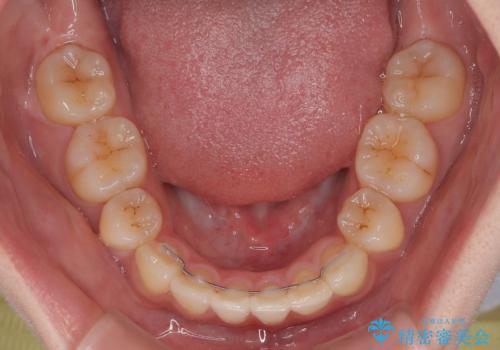

- クリアブラケット

- 3年10ヶ月

- 下顎の前歯が上顎の歯肉に咬みこむくらいに突出した上顎前歯を気にして来院された患者様です。

口元の突出感はないものの、上顎前歯が前方に傾斜して突出しており、前後に大きなズレがあり非常に深い咬み合わせとなっていました。

前突間を改善するため、上顎左右の第一小臼歯を抜歯してワイヤー装置にて矯正治療を行うこととしました。

深い咬み合わせは上顎前歯を引っ込ませる大きな障害となるため、咬み合わせの改善が非常に重要となります。やや期間はかかりましたが、当初狙った通りの仕上がりで治療を終えることができました。